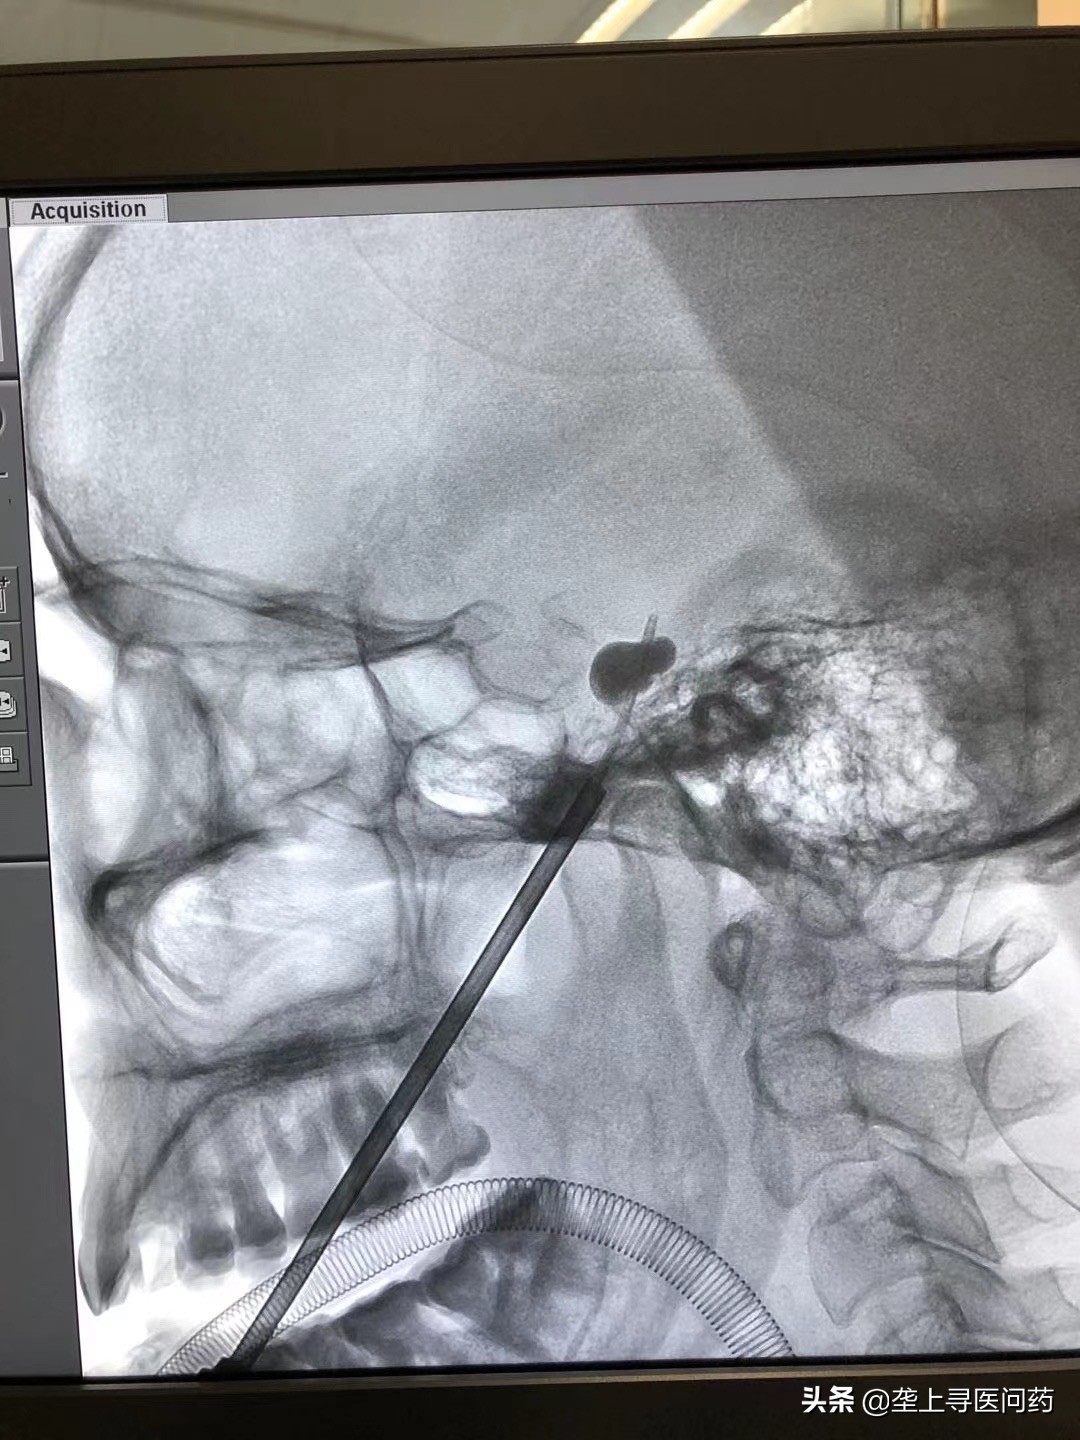

舒凯介绍,三叉神经痛在药物治疗无效时可选择手术治疗,手术方式有开颅微血管减压术(MVD);经皮穿刺球囊压迫术(PMC);射频热凝术。目前MVD是治疗三叉神经痛最有效的手术方式,但高龄患者难以耐受,且部分患者对开颅手术有恐惧心理,如此例病人;射频热凝术则需要患者术中配合,增加了患者的痛苦及紧张恐惧情绪,并且复发率高。因此经皮穿刺球囊压迫术逐渐成为部分病友的首选。但PMC术式的关键点在于球囊的位置必须准确到达麦克尔氏腔(Meckel cave),即三叉神经半月节所在部位,以往术者更多依赖经验来进行操作。此次手术,我们采用手术机器人辅助定位是湖北省首例,通过术前薄层CT三维重建定位卵圆孔位置,制定好手术计划,在机器人的辅助下将针芯、导管顺着头骨中天然存在的“卵圆孔”抵达颅底的三叉神经上的半月节,精准度可达到0.5毫米,而后导入球囊,注入显影剂使球囊扩张压迫半月节数分钟,就可以让三叉神经的痛觉“失活”,达到“止痛”效果,手术时间短,即刻有效,1-2天出院。手术过程无切口,仅是面部有一个小针眼,术后使用创口贴保护术后创口即可,患者得到满意的疗效。